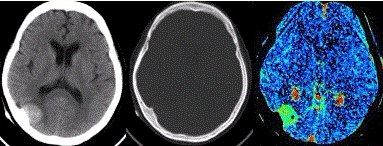

问题 患者女,60岁,头痛半月余。既往体健。腰椎穿刺检查提示脑脊液压力增高。CT及CT灌注表现如下图。 关于该病的影像学表现,不正确的是

选项 A.肿瘤内可出现钙化或脂肪组织 B.MRP:CBV轻度升高 C.恶性肿瘤与轴内肿瘤鉴别困难,MRS可提示诊断 D.MRS:Ala升高 E.MRV显示静脉窦受累

答案 B